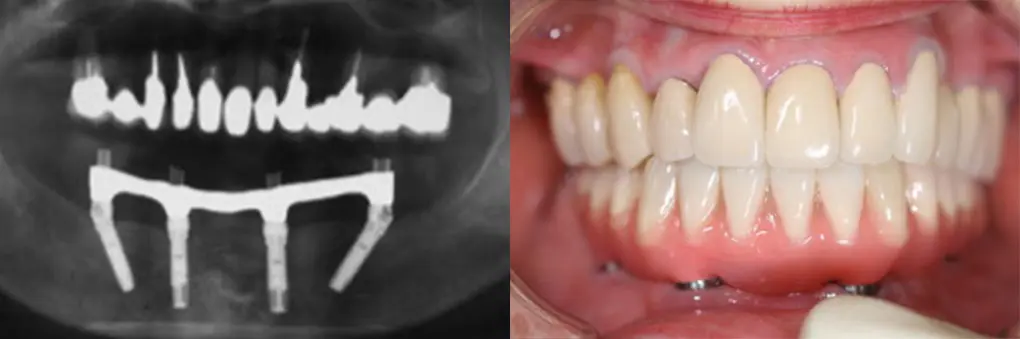

【症例1】All on Fourでインプラント埋入と固定式ブリッジを1日で装着(70代女性)

| 主訴・背景 | 下の前歯がぐらぐらして入れ歯で咬めない |

|---|---|

| 診断・治療前の状態 | 長年義歯を使用していたので下顎臼歯部歯槽骨が吸収 |

| 治療方針・計画 | 抜歯、即時インプラント埋入、即時荷重のAll on Fourで当日固定式ブリッジを装着 |

| 手術・処置内容 | ⚫︎ インプラント埋入部位32,35,42,45 インプラント4本 ⚫︎ 下顎前歯部歯槽骨骨整形、骨造成術 ⚫︎ Nobel Biocare社 ⚫︎ 歯肉付き硬質レジン歯ブリッジ |

| 治療期間・回数 | 仮歯装着まで1日、最終補綴物まで3カ月/治療回数5回 |

| 費用・料金(自費診療の場合) | 2,150,000円 |

| リスク・注意点・術後ケア | 硬質レジン歯の破折、インプラント周囲炎、定期検診 |

| 治療後の状態・経過写真 | 入れ歯による咬合時の痛みがなく、入れ歯と違ってよく咬める 8年経過良好で定期検診に6カ月毎来院 |

| まとめ・院からのコメント | 予算の関係上、人工歯に硬質レジン歯を選択したため咬耗した人工歯交換を次回定期検診時行う予定です。 |